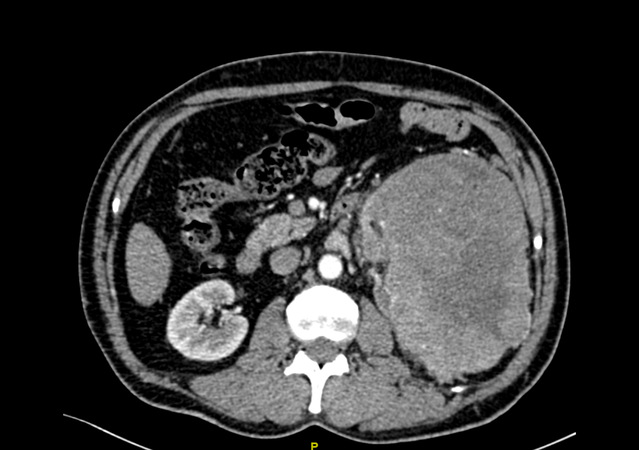

经过CT等检查,发现陈先生的左边肾脏上长了一个巨大的肿瘤,大小约16.6cm*11.1cm,也正是因为这个原因,导致了腰痛、血尿、排尿困难等一系列症状。

苏州九院泌尿外科团队仔细分析了患者的病情、症状以及影像学检查,发现陈先生体内的这一颗“定时炸弹”比既往所处理过的任何一例肾脏肿瘤都要庞大,而且已经充满了患者的后腹腔,更为棘手的问题在于肿瘤恶性可能极大,供养这颗肿瘤生长的血管,也密密麻麻的盘曲在肿瘤周围,给手术治疗带来了极大的困难。如果按照既往的治疗方案,对于如此巨大的肾脏肿瘤,而且同时合并肿瘤出血带来的粘连等一系列困难,往往选择开放手术,也就是老百姓口中的“开大刀”。但是众所周知,开放手术存在切口长、手术创伤大、术后恢复缓慢以及术后并发症多等诸多缺点。思虑再三,经过泌尿外科科内讨论后,最终决定给陈先生实行了腹腔镜下微创手术,减少手术带来的损害及痛苦。